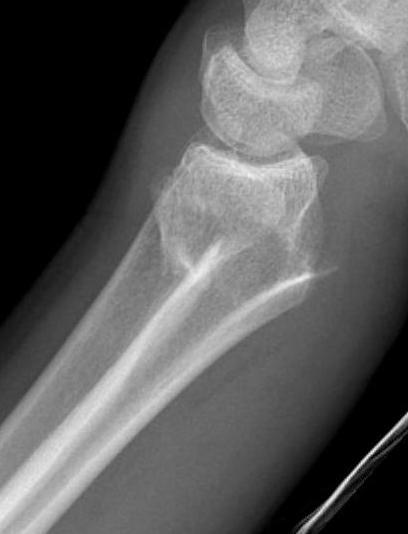

Distal radius fracture with shortening and dorsal tilt

Articular incongruency > 2 mm

Sigmoid notch disruption and DRUJ instability